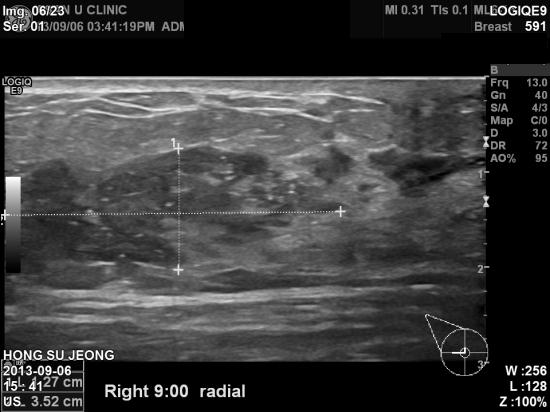

우측유방에 1년정도 전부터 만져지던 혹이 지속적으로 커졌으나

바빠서 신경못쓰고 지내다가

우측 유두, 젖꼭지에서 진물이 나오기 시작하여 검사위해 내원하신 30세 여자분이십니다.

유두까지 퍼진 암의 초음파 직경은 6cm 정도로 크지만

조직검사 결과가 상피내암으로 나온것과,

액와 림프절이나 다른 부위 림프절 전이가 의심되지 않는 것으로 보아

최종 수술결과는 0기암일 수도 있을 것 같아

불행 중 다행이라 여겨지는 증례입니다.